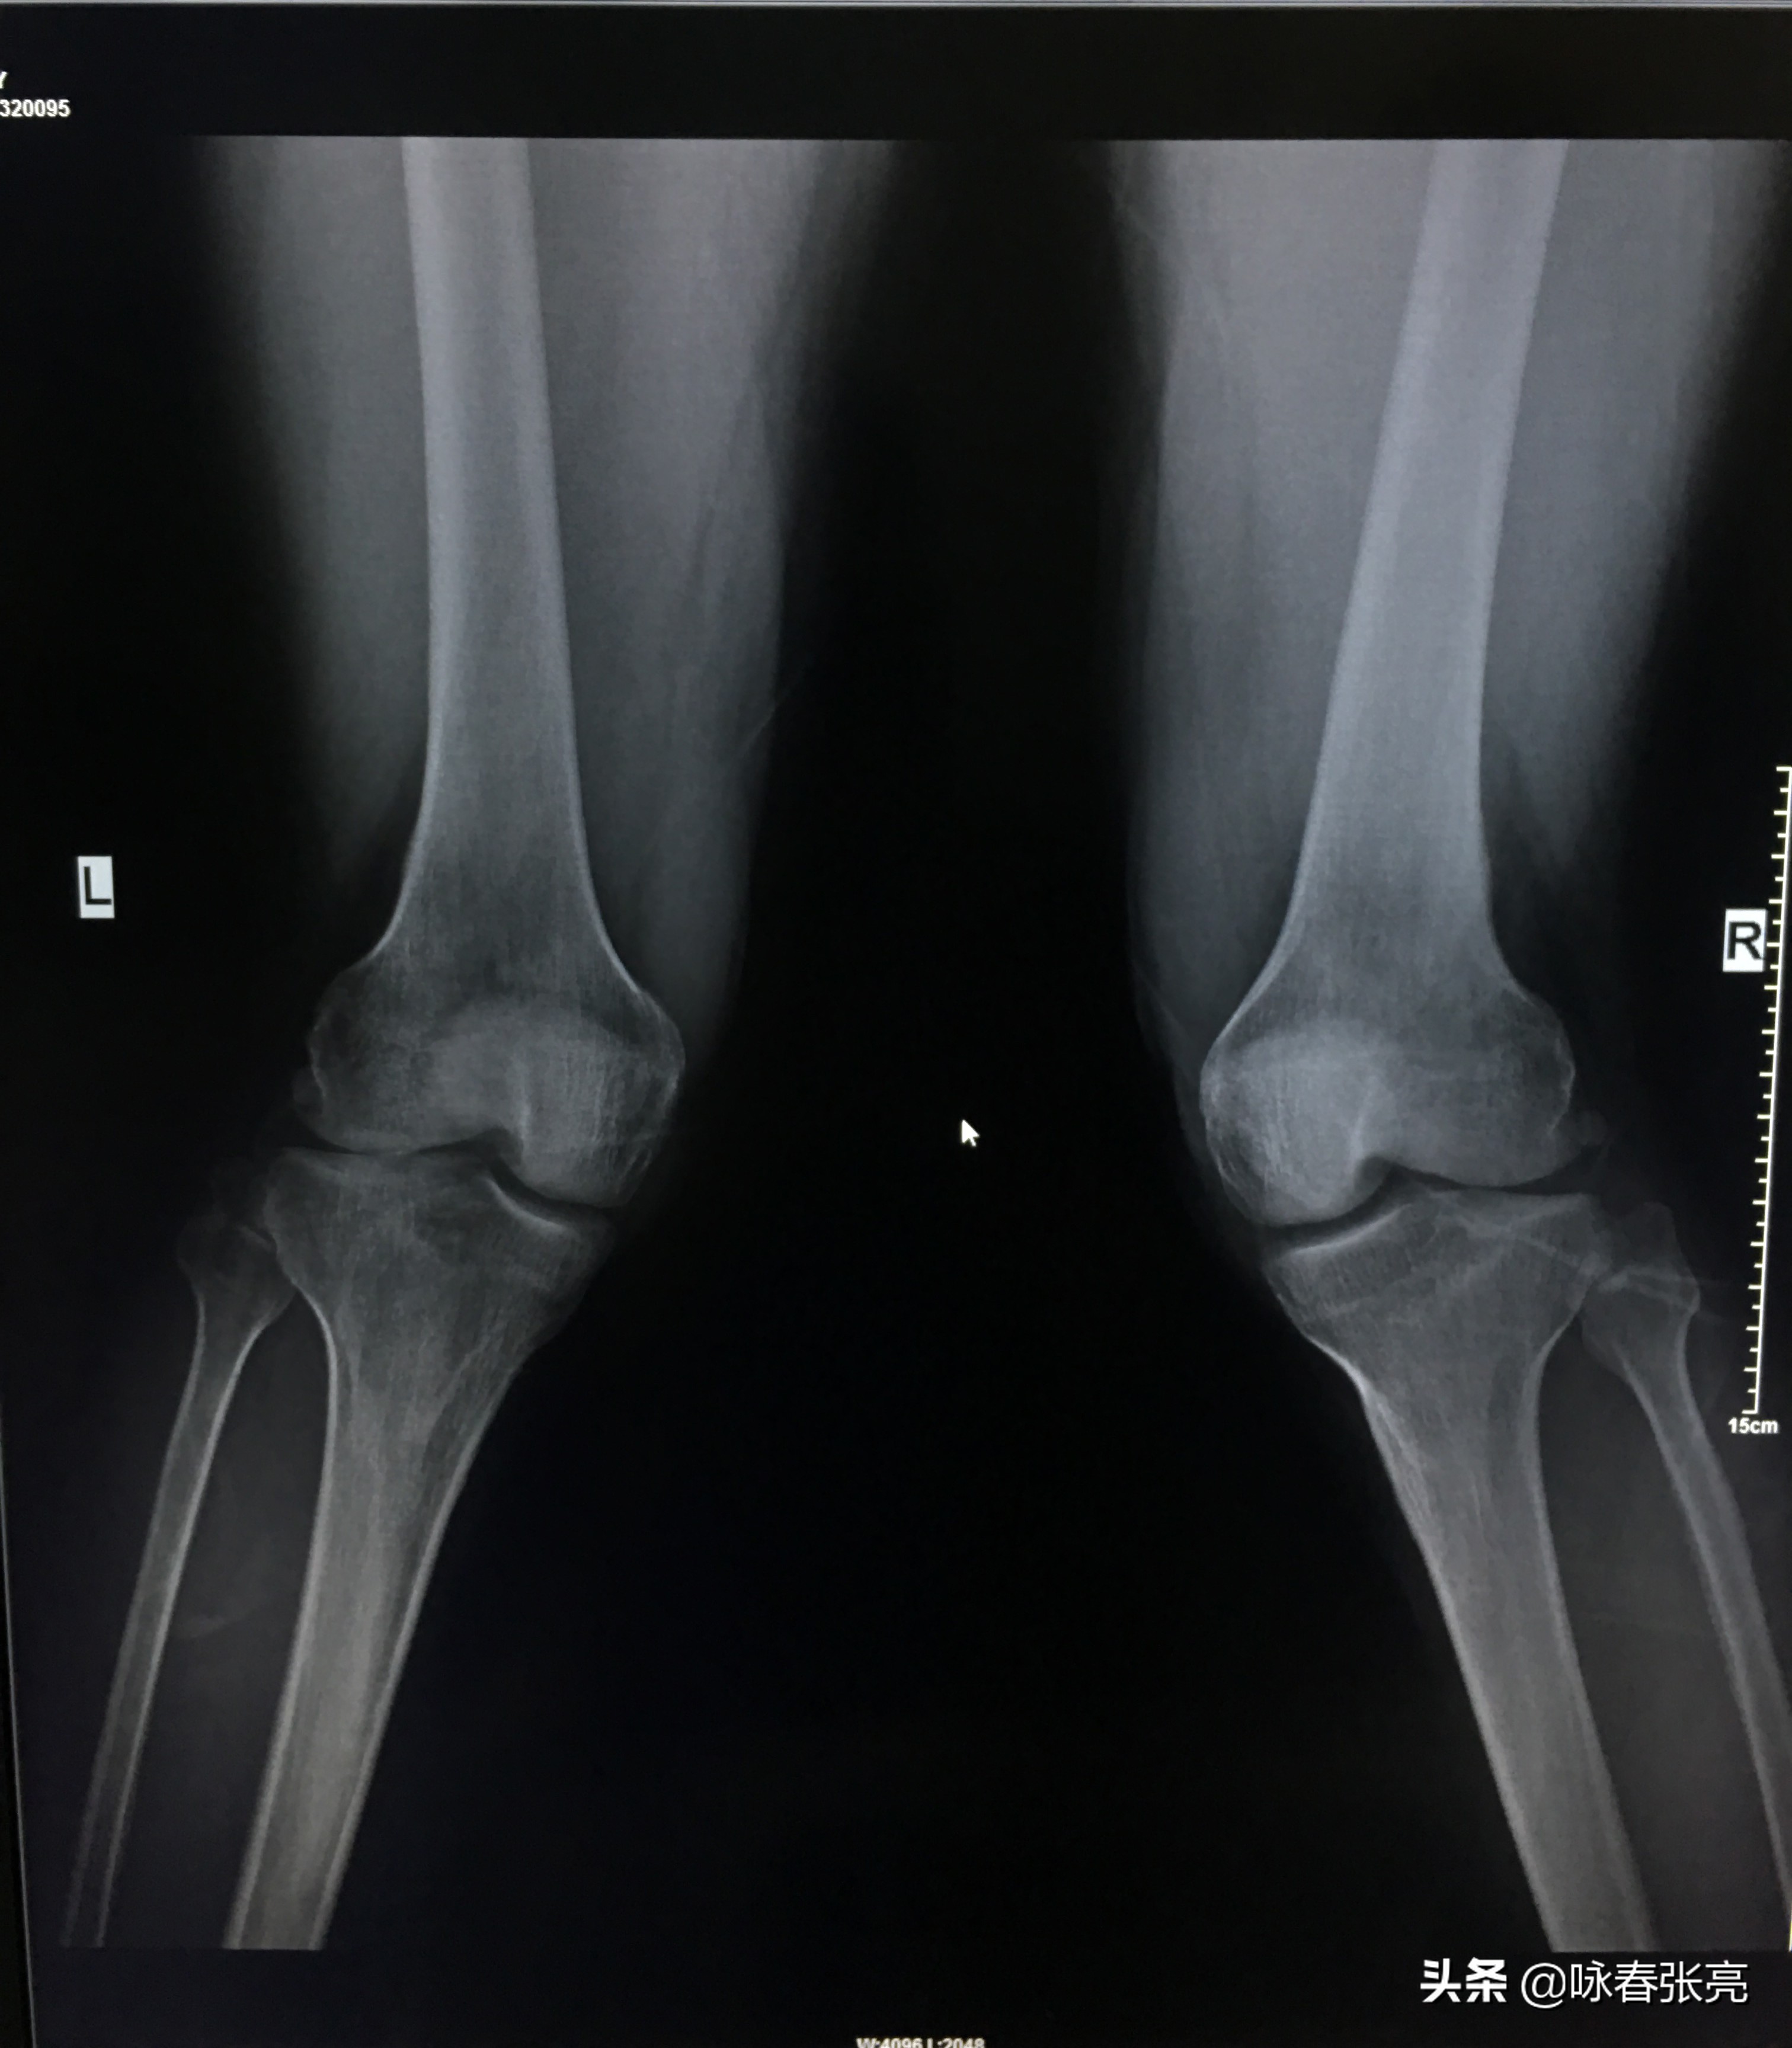

咏春拳钳羊马 DR